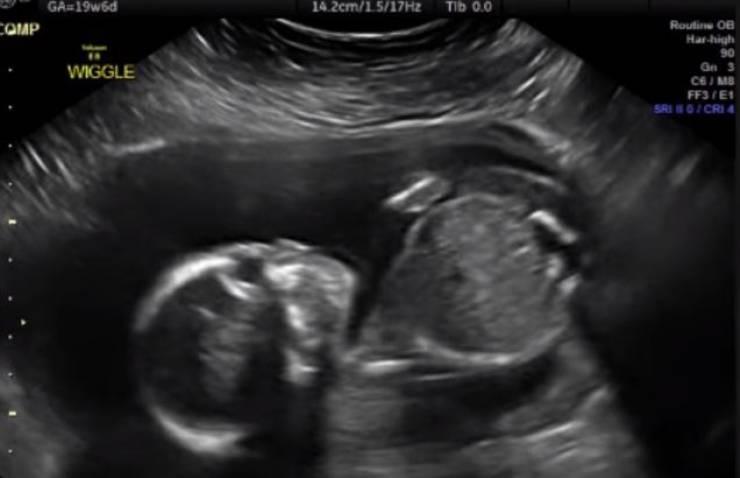

لا يتذكر الناس شيئا عما فعلوه حين كانوا في أرحام أمهاتهم، لكن باحثين في الطب كشفوا عدة أمور يقوم بها أي جنين قبل قدومه إلى الحياة.

وبحسب موقع "ساينس فوكس"، فإن الجنين يقوم في بداية تشكله، بإحداث تغيير في الأوعية الدموية داخل الرحم لأجل إنشاء المشيمة التي تقوم بعملية حيوية خلال فترة الحمل.

وبفضل هذه المشيمة، يقوم جسم المرأة الحامل بنقل الغذاء والأوكسجين إلى الجنين داخل الرحم، وعلاوة على ذلك، ينقل الفضلات إلى الخارج، لكن التفاعل بين الأم والطفل لا يقف عند هذا الحد.